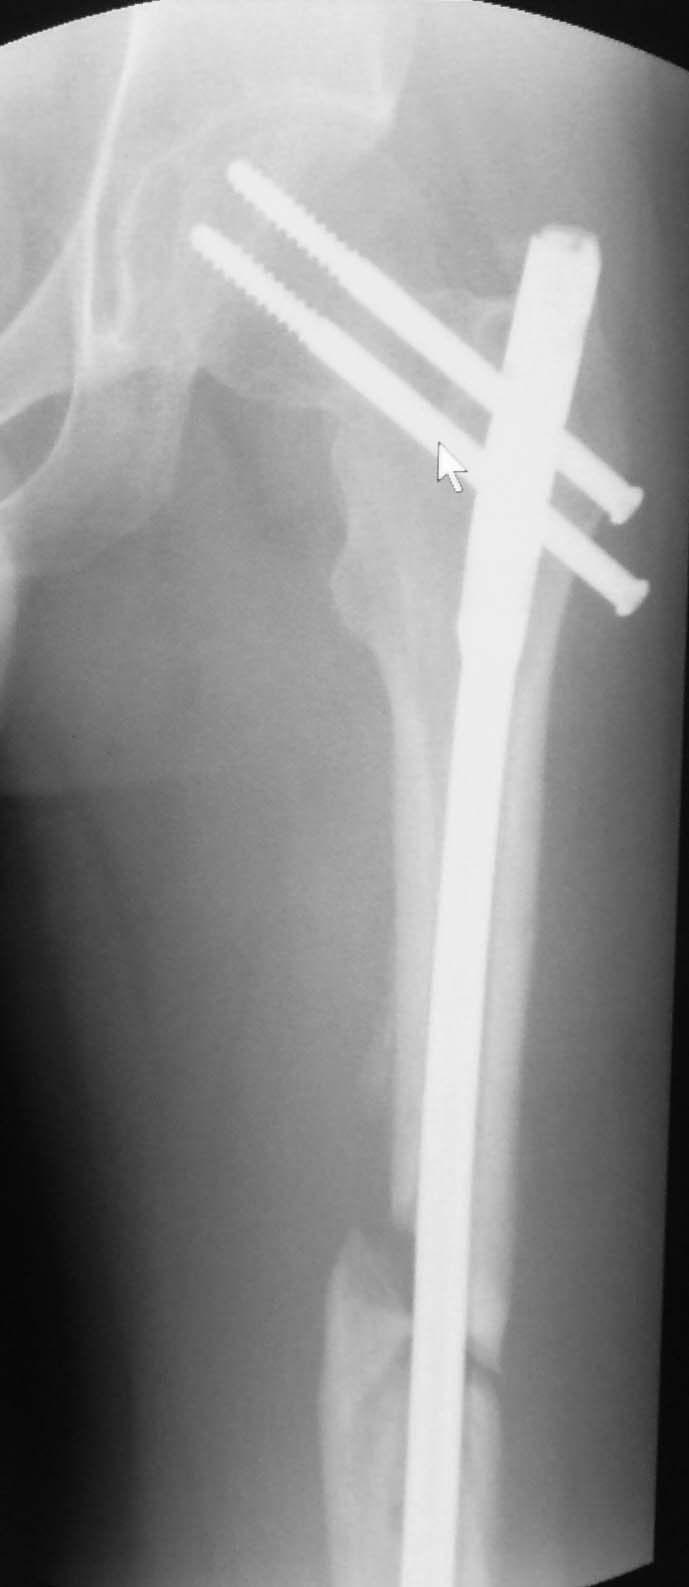

У Синтеза специально для таких двойных переломов есть латеральный бедренный гвоздь, позволяющий увеличить расстояние между гвоздем и линией перелома шейки за счет смещения кнаружи точки введения гвоздя. Во вложении - трехлетней давности пример: остеосинтез выполнен через полтора месяца после травмы, вполне удалась закрытая репозиция проксимального перелома. Единственный непонятный для меня момент такой операции - невозможность динамизации диафизарного перелома без удаления фиксаторов из головки. В представленном случае шейка срослась быстро, а вот диафиз - только после удаления верхних винтов и установки винта в динамическое отверстие в подвертельной области.

Действительно, риск неудачи меньше, если делать раздельно (шейку - винтами или DHS, диафиз ретроградно). Одной жеезкой делать труднее, а еще и без ЭОП. Но можно.

1)Удаление имеющейся конструкции, реостеосинтез длинной версией GN,PFN, латеральным бедренным гвоздем. обязательным условием проксимального блокирования является сохранение спиц в шейке до окончания блокирорвания.

2)Ретроградный БИОС и винты в шейку

3)Накостный остеосинтез с применением длинной пластины с винтом DHS+антиротационный винт в шейку бедра.Применение двух пластин может быть проблематичным технически и создать нежелательную зону напряжения в в/3 диафиза вплоть до периимплантного перелома в последующем.